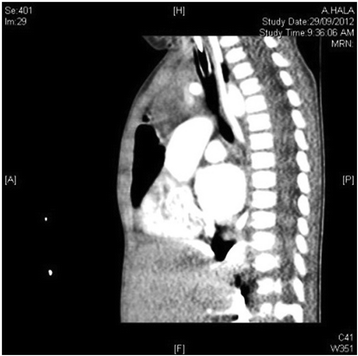

Case presentation: Here, we describe a 1-year-old Saudi female child with respiratory distress at birth. The child then had recurrent lower respiratory tract infections, bilateral lung emphysema with basal atelectasis, bronchospasm, pulmonary artery hypertension, and oxygen and mechanical ventilation dependency. Molecular testing showed a new pathogenic variant of one copy of c.3153dupC in exon 21 in the FLNA gene.